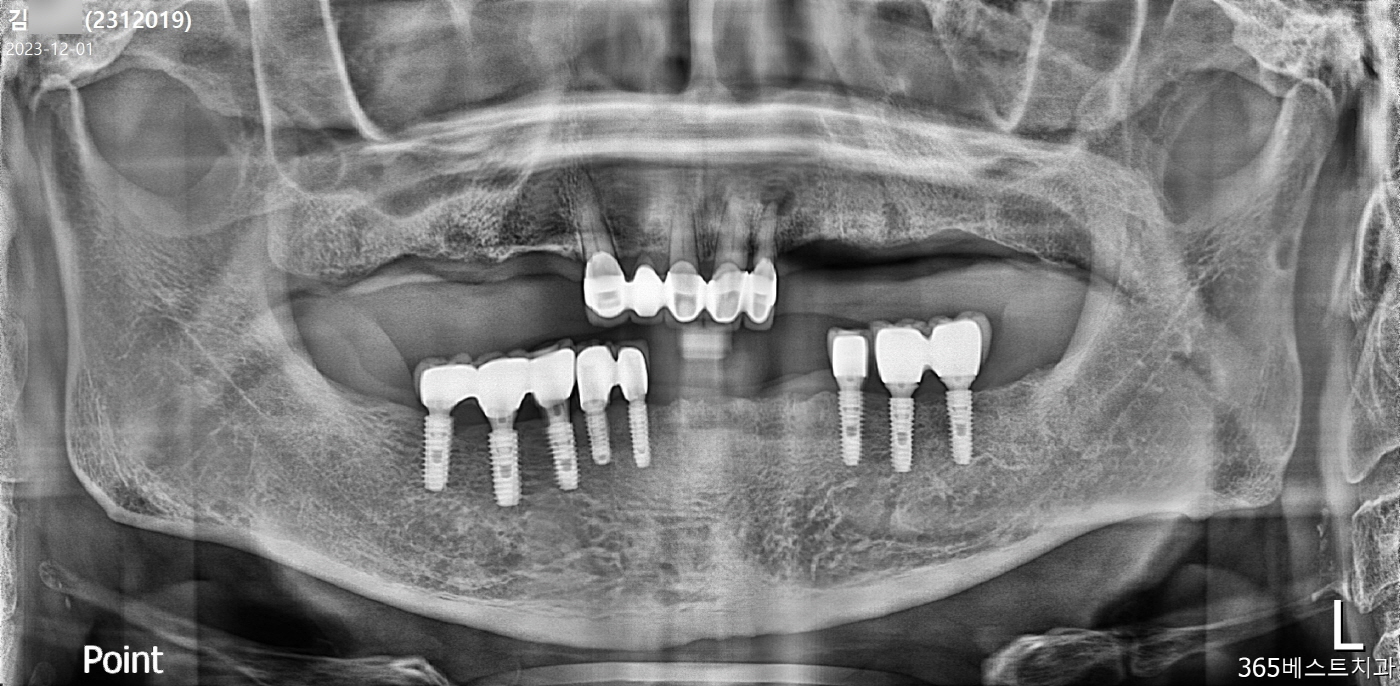

[임플란트] 고령환자 전체임플란트

(전)

(후)

*단, 모든 임플란트 시술은 실패의 가능성이 있음